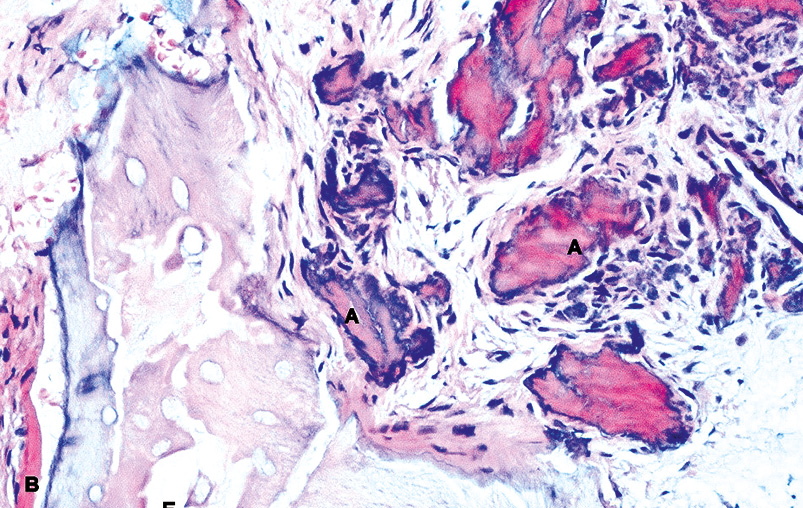

Отмечается пролиферация эпителия с наползанием и врастанием эпителия в область дефекта кости (рис. 2). Массивное врастание эпителия подавляет продукцию факторов роста кости, нарушаются молекулярно-клеточные механизмы и межтканевые взаимодействия. Эпителиально-соединительнотканный комплекс выстилает костную поверхность дефекта замещая надкостницу. Это приводит к блокированию репаративного остеогенеза в области костного дефекта.

Рис. 2. Мягкотканый фрагмент из области костного дефекта. Врастание эпителия в подлежащую ткань. Окраска гематоксилин-эозин, ×200.

Fig. 2. A soft-tissue fragment from the area of the bone defect. Ingrowth of the epithelium into the underlying tissue. Hematoxylin-eosin stain, ×200.